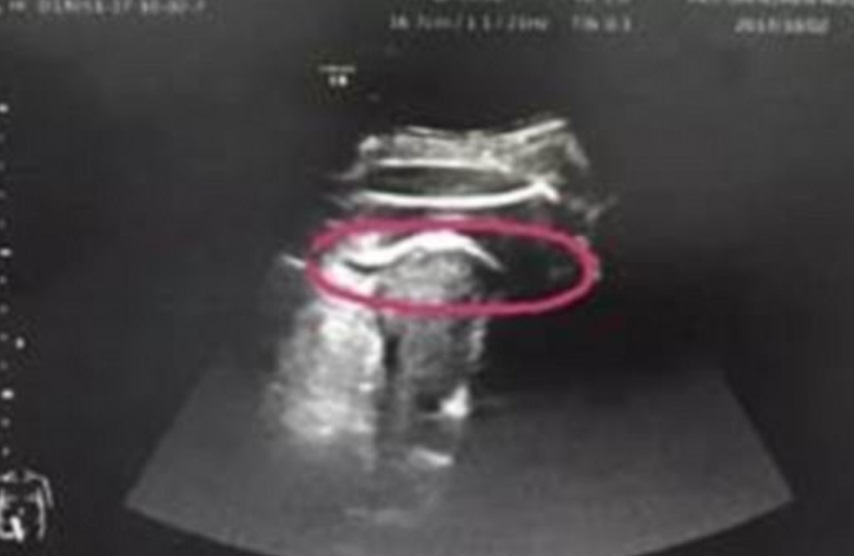

[Una mujer, identificada como Zhang, experimentó un caso que médicos lo han llamado “extremadamente raro” cuando su hijo aún no nacido le dio un puntapié suficientemente fuerte que atravesó la pared de su útero, según el diario Daily Mail.

El médico de Zhang, Zhong Shilin, dijo que el útero de la mujer tenía una ruptura de casi 3 pulgadas de largo. El líquido amniótico de Zhang también había comenzado a fluir hacia su abdomen.

El bebé nació aproximadamente 10 minutos después de la cesárea de emergencia, según el Hospital Shenzen de la Universidad de Beijing, China.